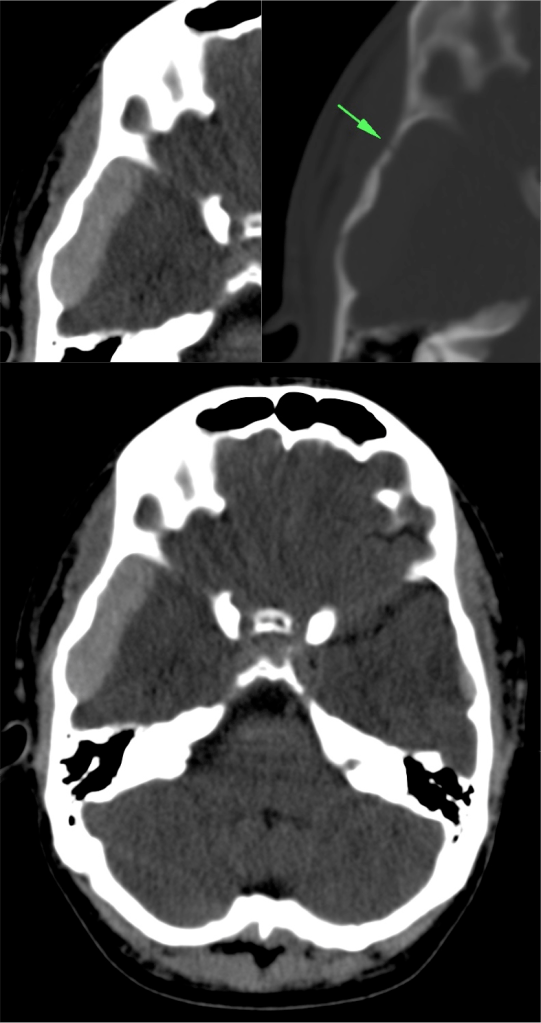

Con ventana de hueso.

Las reconstrucciones 3D-VR aumentan la capacidad diagnóstica de las fracturas desplazadas y no desplazadas.

La presencia de fractura no se correlaciona con la severidad del daño cerebral, sin embargo, la incidencia de hemorragia intracraneal es mayor en pacientes con fractura que en los que no la presentan. Al mismo tiempo, el 25% aprox. de pacientes con daños cerebrales fatales no muestran fractura de cráneo.

- Fracturas lineales = las más frec. -> baja incidencia de daño cerebral.

- Fracturas con hundimiento -> asocia contusiones y roturas durales.

- Fracturas de la base -> pueden ser transversas o diagonales, éstas con mayor índice de mortalidad. Pueden causar ceguera, afectación de pares craneales, pédida de audición, fuja de LCR. En las fracturas que afectan al canal carotídeo en su porción petrosa, merece la pena realizar un angioTC.